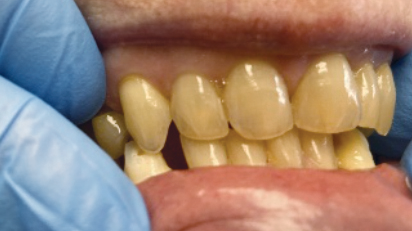

Concomitant Temporomandibular Total Joint Replacement and Orthognathic Surgery

Abstract Facial differences and temporomandibular joint (TMJ) disorders often coexist. Some dentofacial deformities can be a common primary cause of TMJ pathology or develop as a secondary result of joint disease. Patients with these concurrent pathologies benefit from simultaneous surgical management of both issues, typically involving OGS and alloplastic total joint reconstruction (TJR). This article … Read more